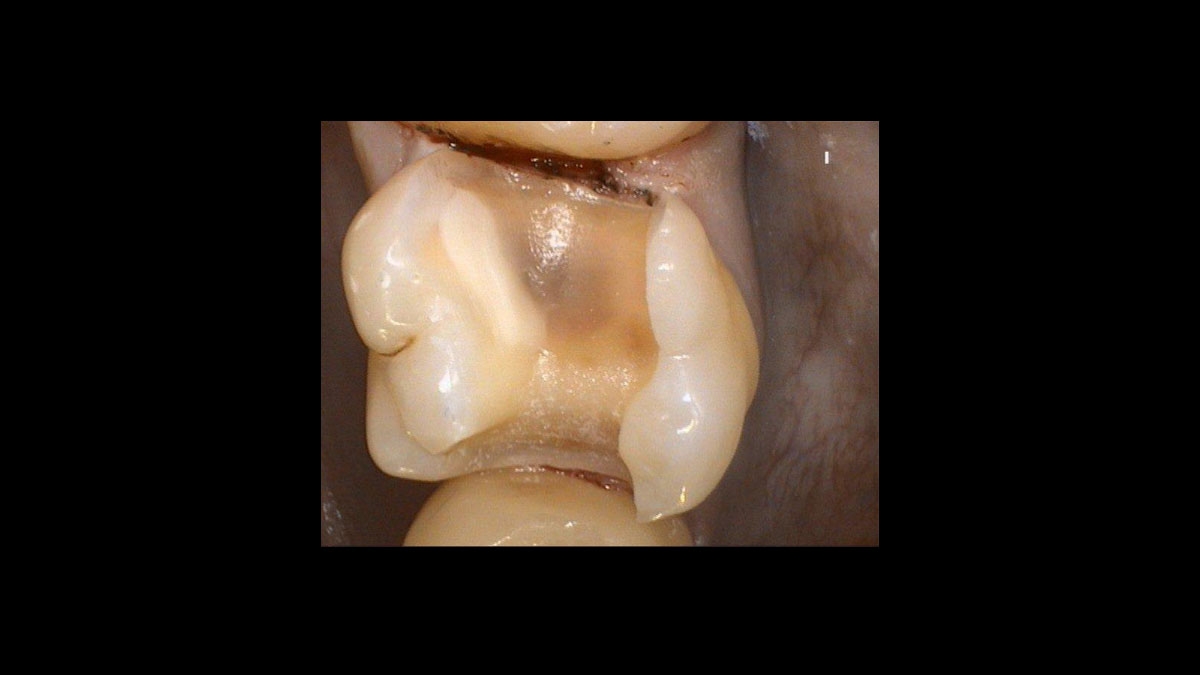

After the Hemostasis

Digitalised imprint of the tooth